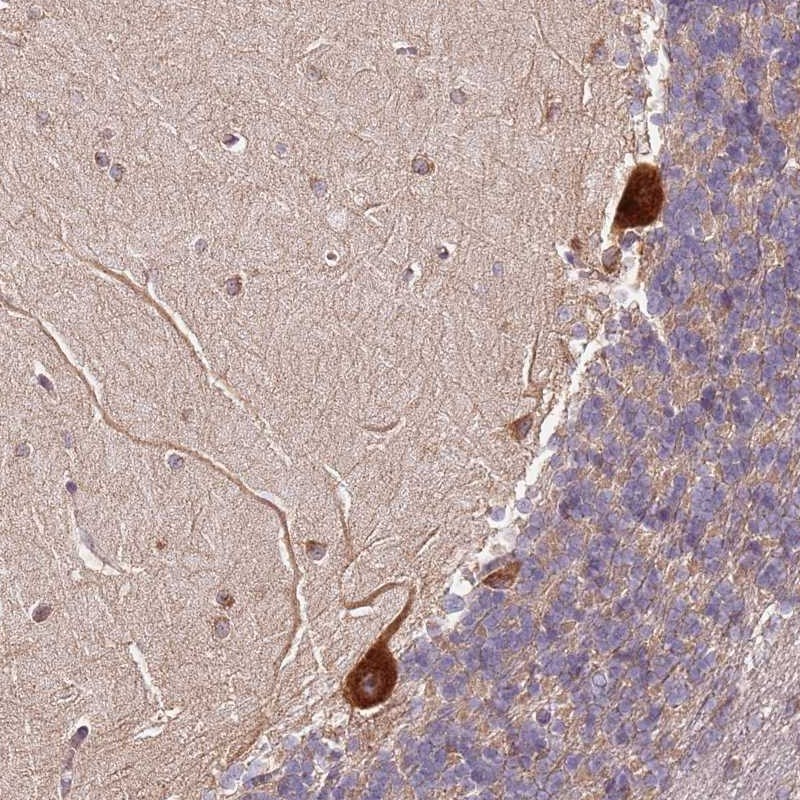

Immunohistochemical staining of human cerebellum shows strong cytoplasmic positivity in Purkinje cells.